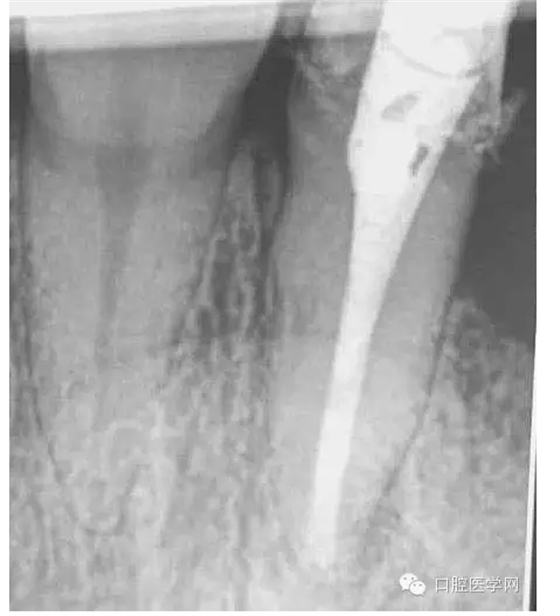

患牙有嚴(yán)重叩診不適。根尖片明確的顯示了牙根根尖喇叭口及根尖均有低密度影像。2年前有外傷史,右上側(cè)切牙缺失。

4.準(zhǔn)備放置橡皮障(由于拍片是較遠(yuǎn),所以,橡皮章暫時(shí)取下),去除暫封材料。在顯微鏡放大視野中,蔣調(diào)拌好MTA輸送至根尖部。

5.待MTA凝固后進(jìn)行熱牙膠充填。